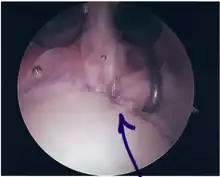

SLAP Tear

Repair of SLAP Tear